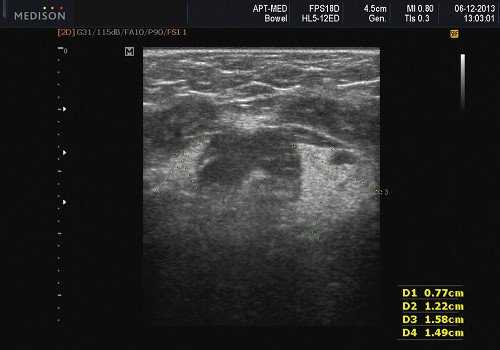

Плеоморфная (полиморфная) аденома (смешанная опухоль СЖ) - аденома СЖ, построенная из двух типов клеток: эпителия протоков и миоэпителиоцитов. Макроморфологическая картина. Опухоль обычно представляет собой эластичный или плотный узел дольчатой серовато-белой ткани, как правило, инкапсулированный частично. Типичной для плеоморфной аденомы является так называемая хондроидная строма, напоминающая гиалиновый хрящ. Варианты эхографического изображения плеоморфных аденом представлены на рисунке 8.